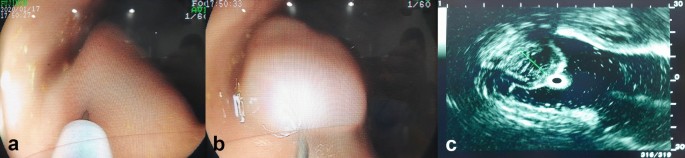

Three solutions were examined—normal saline, Endo-Ease (UNIMED Pharm. Inc., Seoul, Korea), and MC-003 (Mcnulty Pharma Co., Ltd., Seoul, Korea). All solutions were stored and prepared at room temperature. Six male pigs between five and six months old (weighing 50–60 kg) were prepared for the study. They were anesthetized with xylazine, tiletamine, zolazepam, and isoflurane. Mechanical ventilation of the prone animals was provided during anesthesia after insertion of an endotracheal tube, and vital signs were monitored. All endoscopic procedures were performed by an experienced board certified endoscopist. Using a 23-gauge needle through the accessory channel of the gastroscope (XL-4400, Fujinon, Saitama, Japan), 5 mL of normal saline, Endo-Ease, or MC-003 were injected into the gastric submucosal layer at a separate site (minimal distance of 2 cm) in each pig, respectively. After making 18 submucosal fluid cushions in total, ultrasonography was performed by the same endoscopist at 5, 10, 15, 20, 25, 30, 35, and 40 min-time points after injection. The height of each submucosal fluid cushion was measured using an SP-900 ultrasound device (Fujifilm, Japan) (Fig. 1). Anesthesia was maintained until the last ultrasound examination was completed (40 min after submucosal injection). The pigs were euthanized after a specified period for histopathologic examination; they were euthanized using suxamethonium while under anesthesia induced with a mixture of tiletamine and zolazepam. Three of the six pigs were euthanized 2 h after the submucosal injection to assess immediate histological changes. The rest were euthanized 5 days after the procedure to examine delayed histological changes. Abdominal radiographs of each pig were obtained before and after submucosal injection and before euthanasia. Laboratory blood tests for inflammatory markers and blood chemistry were performed prior to submucosal injection and euthanasia. After euthanasia, the submucosal injection site in the stomach wall was identified and assessed histologically. The tissues were fixed in 10% formalin for more than 24 h, embedded in paraffin, sectioned into 4 μm thickness sections, and stained with hematoxylin and eosin and Masson’s Trichrome reagent. The pathologist reviewed tissue edema, congestion, inflammation, and hemorrhage around the injection site, and any significant changes were recorded based on a defined grading scale ranging from grade 0 (no specific change) to grade 1 (minimal), grade 2 (slight), grade 3 (moderate), and grade 4 (severe).